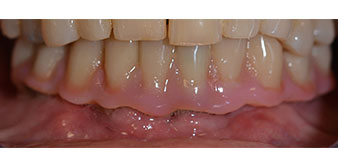

Im Anschluss erfolgt die Abformung und Bissnahme, sodass die Zahntechniker umgehend mit der Anfertigung der provisorischen Arbeit beginnen können. Diese wird im Anschluss am gleichen Tag eingeschraubt (Abb. 17 und 18).

Nach der Zeit, die für die Osseointegration benötigt wird, kann die endgültige Abformung der Implantate erfolgen und entsprechend die endgültige Arbeit angefertigt werden (Abb. 19 und 20). Hier können Behandler und Patient gemeinsam entscheiden, ob diese eine Keramik- oder Kunststoffverblendung, ein Zirkon- oder Metallgerüst bekommen soll. Im vorliegenden Fall hat sich das Team um Dr. Pascu, aufgrund der unklaren Prognose der Oberkieferbezahnung und des elongierten Zahnes 24, für eine Kunststoffverblendung entschieden. Diese ist im Allgemeinen wesentlich einfacher umzustellen und der neuen Situation im Oberkiefer anzupassen.